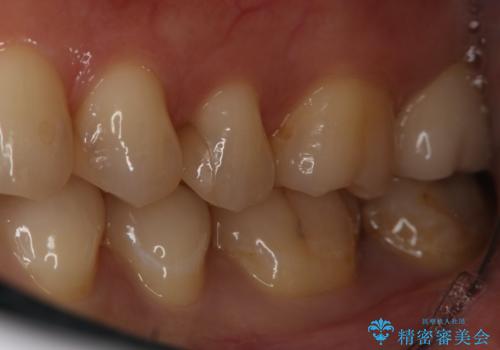

- 左下6、7番の虫歯をセラミックにて治療を希望された患者様です。

切削量を考慮してセラミックインレーを選択しました。

7番は虫歯が深かったのでCR裏層した上で形成、印象をしています。